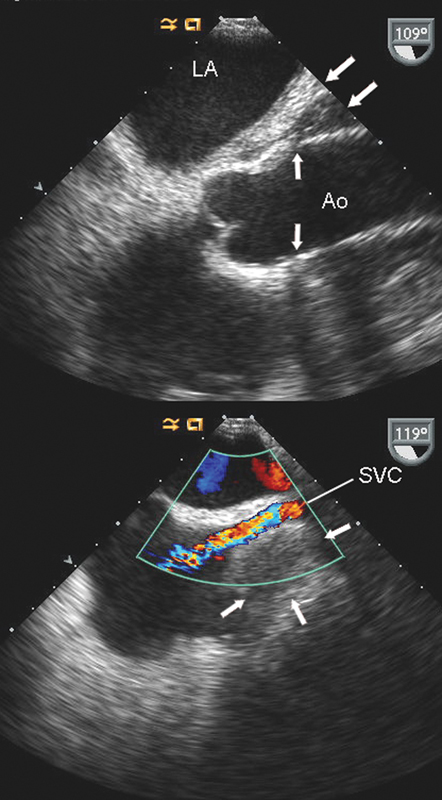

فحوصات تشخيصية لبعض امراض القلب والشرايين التاجية